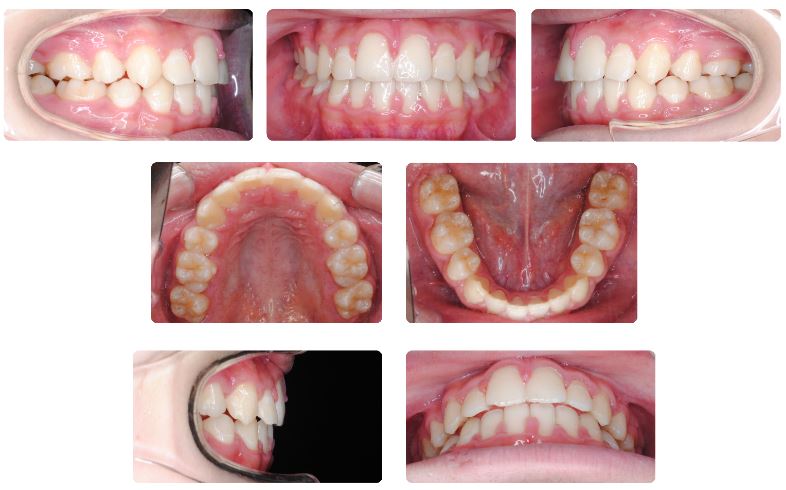

治療期間は1年8か月でした。

術前と術後を比べますと口元がすっきりして口がとても閉じやすくなったとのことでした。